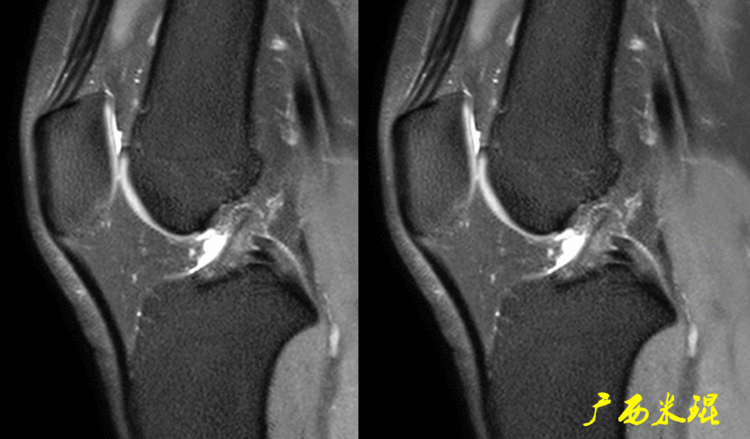

(2)隐窝隐窝是半月板后角与关节囊之间的正常凹陷,与体位等有关,可有可无,一般情况下积液越多隐窝越大,有上下之分,下面这张MR矢状位片见到的是上隐窝,紧贴半月板、光滑、不连通是其特点,也是鉴别要点。

下面这张MR矢状位片见到的是下隐窝,也紧贴半月板、光滑、不连通。

隐窝需要与半月板囊肿鉴别,下面这张MR矢状位片见到的是内侧半月板后角损伤并囊肿形成,与隐窝是有明显区别的。

隐窝还需要与半月板关节囊分离鉴别,下面这张MR矢状位片见到的内侧半月板后角与关节囊完全分离,周围水肿,胫骨内侧平台后方骨水肿;而隐窝是不会连通的。